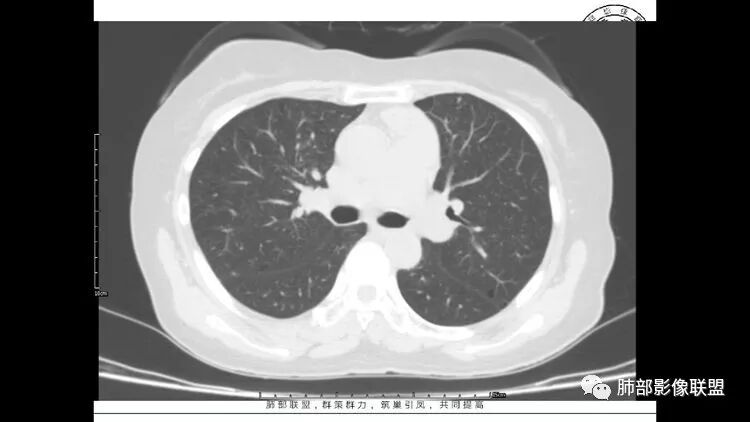

LIP影像重要线索一句话:

双肺下叶分布为主的间质改变(磨玻璃影、小叶间隔增厚)、散在气囊影(常有血管贴边)、边界不清小结节

双肺多发散在斑片状磨玻璃密度影及大小不等的薄壁含气囊腔,下肺相对较多较大。双肺多发结节,界清,边缘光滑,分叶不明显。右肺下叶前外基底段散在斑片树芽。前上纵膈偏左侧不规则软组织团块,密度不均,其内可见不规则纤维样低密度,周围簇状小淋巴结。考虑1淋巴细胞间质性肺炎。2考虑纵膈胸腺淋巴瘤。

老年女性,长期使用激素史。双肺多发散在斑片状磨玻璃密度影及大小不等的薄壁含气囊腔,下肺相对较多较大。双肺多发结节,左肺上叶结节相对较大,界清,边缘光滑,分叶不明显。右肺下叶前外底段散在树丫。前上纵膈偏左侧不规则软组织团块,颗粒感,偏软。肺内囊腔及磨玻璃影考虑淋巴细胞间质性肺炎,或淋巴管肌瘤病。纵膈团块考虑淋巴管瘤。两者结合,考虑淋巴细胞增生病变。右肺下叶散在树丫,结核待排。双肺结节性质待定。